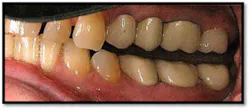

TX FM Perioscopy with local anesthetic FM LANAP Surgical Procedure •bone sounding was performed on all teeth included in this procedure •occlusal adjustment performed resulting in reduction in centric prematurities •Orthodontic referral for anterior spacing •3 month periodontal maintenance14 months post TreatmentPocket reductions of up to 4mm

The patient now has a stable dentition and has moved forward with Invisalign orthodontia to correct the overbite and spacing in her anterior teeth.

The posterior crowns still present a challenge to keep clean and will be scheduled for replacement post orthodontic treatment.